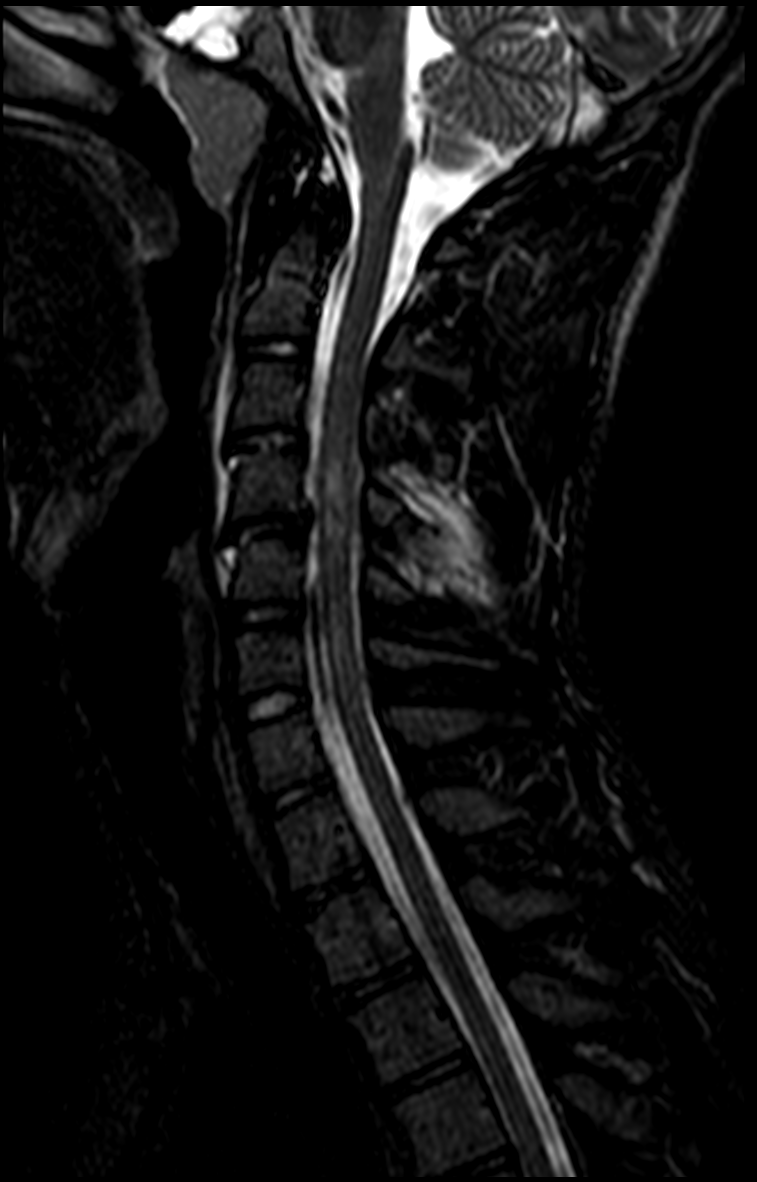

RM SAGITAL (STIR)